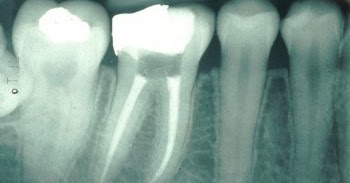

The main sensory nerve in the lower part of the jaw can be injured during a root canal procedure due to the overextended filling of materials. Dec 1 20Mechanical nerve injuries during endodontic treatment may be classifie based on the time course and the potential sensory recovery into: Neuropraxia (cases in which there is a brief altered sensation Axonotmesis (partial damage to the nerve fibers that may fully recover within 2months and Neurotmesis (a nerve that has been entirely cut, with poor prognosis for recovery) (Rosen, 2014). Root Canal Symptoms: Ways to Tell If You Need a Root Canal Aug 2 20Nerve Damage Caused by Over-filled Root Canals by Robert J. Six Causes of Pain After a Root Canal - Angela S. Pain after root canal: What is normal, when to get help. Jan 3 20A look at pain after a root canal, a common complaint that can last for some time.

Inferior alveolar nerve damage could cause numbness or pain in the chin, lips, and gums, as well as a tingling sensation or a burning ache.

Dental Malpractice: Errors that Cause Nerve Damage Jul 1 20Inferior Alveolar Nerve Damage. A lack of sensation, numbness, pain, or discomfort in the lip or chin is an indication of overfill of the lowerback teeth. Fleming As a 20study indicates, overfilling the roots with sealant during a root canal procedure can cause permanent nerve damage if not treated promptly.

Included is detail on when to get help and managing root canal pain. The nerve endings in the periodontal ligament are extremely sensitive and the dead pulpal tissue creates an environment that provides nutrition for the bacteria that have invaded the root canal and caused the necrosis to occur in the first place. Damage to the inferior alveolar nerve may also be caused by wisdom teeth extraction, or could be the result of poorly placed dental implants or the overfilling or overworking of a tooth during a root canal surgery. Causes of Bump on Elbow: Injury, Cyst, Bursitis, and More Jan 3 20Clusters of itchy, small blisters and bumps, mostly on the elbows, lower back, buttocks, knees, and back of the head. is, in many ways, a very young age, but high blood pressure becomes more dangerous after this point. Best Knee Braces for Torn ACL (Before and After Surgery.

Root canals have blood vessels for delivering nutrients to teeth and nerves that identify various influencing factors, such as col heat, and pressure. Stagnant hypoxia occurs when blood flow is inadequate, or there is blood pooling. They are designed to improve the function of the knee when a particular ligament has been damaged and the normal knee.